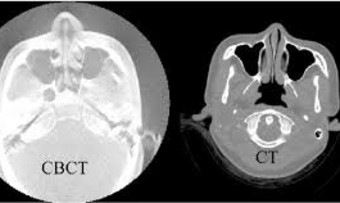

CT / CBCT Imaging

I use high-resolution imaging to confirm sinus blockage, detect dental-related inflammation, and support accurate odontogenic sinusitis diagnosis.

What diagnostic tests are needed?

Odontogenic sinusitis diagnosis typically requires nasal endoscopy and CT or CBCT imaging. These tests confirm whether a dental source is affecting the sinus and guide a personalised treatment plan.